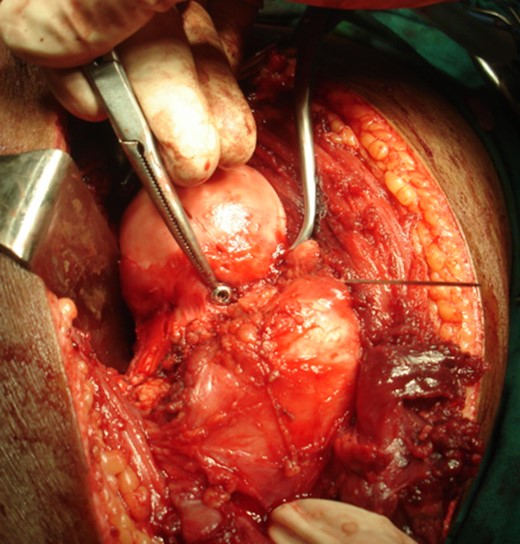

The right hip joint was approached via the Kocher-Langenbeck approach, fracture site was exposed with removal of fibrous tissue and the fracture involved mostly the infrafoveal non-weight bearing surface of the femoral head (Fig. 4). Following reduction of fracture, femoral head was fixed with two 4 mm cannulated cancellous screws that were introduced over a guide wire from the non-articular part under C-arm guidance (Fig. 5). Open reduction and plating was performed for the ipsilateral femoral condylar fracture. Closed reduction and intramedullary nailing of left femur was performed in the same sitting. The immediate postoperative X-ray was satisfactory (Fig. 6). The postoperative period was uneventful.